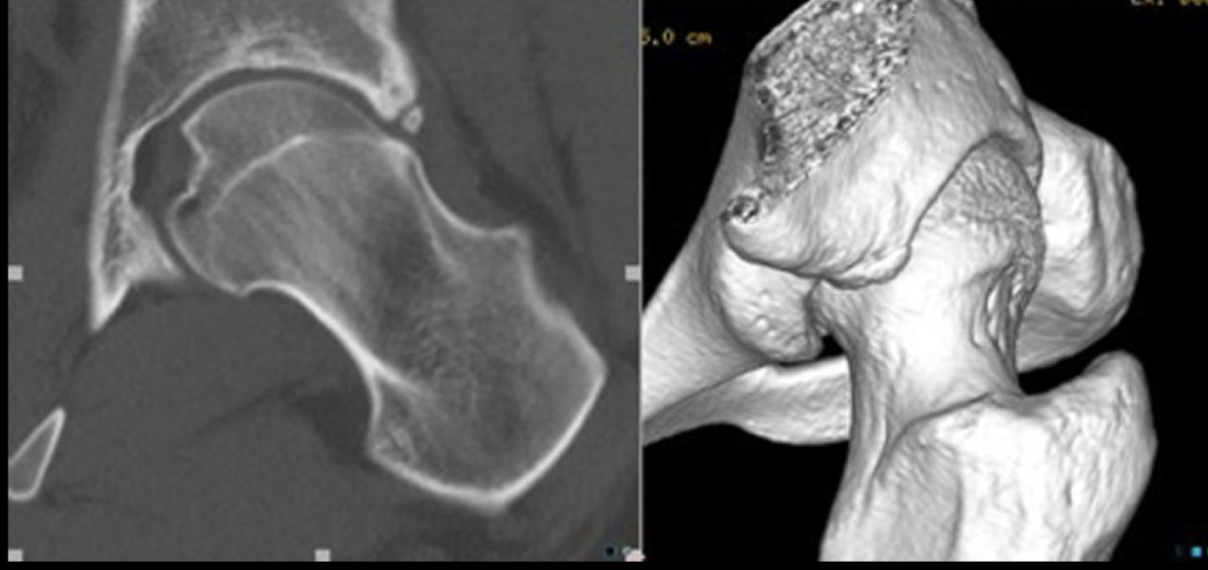

6

Q

TC PZFAC

A

Permite mejor evalucación anatómica

Reconstrucción 3D